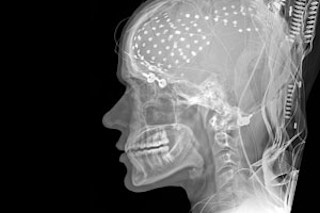

Exactly how these drugs work their magic remains unknown, but stimulants like Ritalin and modafinil influence the neurotransmitters dopamine and norepinephrine, which are essential for attention and memory skills. Both drugs inhibit reuptake, or reabsorption, of these neurotransmitters by neurons, thus prolonging their action. Modafinil also indirectly alters the action of glutamate, the main neurotransmitter used by neurons in the brain to send signals down the line. The center of action for all these drugs, says University of California at Davis psychiatrist Michael Minzenberg, is the prefrontal cortex, the part of the brain that is responsible for executive functions like sorting out conflicting thoughts, making choices, predicting events, and exerting social control.

Specializing in research on modafinil, Minzenberg has captured the drug in action through functional MRI (fMRI) scans, which map brain activity through changes in blood flow and oxygenation as subjects engage in particular mental processes. In one Minzenberg study, 21 healthy research subjects received either modafinil or a placebo on different days as they took a standardized test. Modafinil helped subjects perform significantly better on the task.

Researchers also saw the shift in prefrontal cortex activity right on the fMRI map. When an individual is not concentrating on a complex task, neurons in that part of the brain fire sporadically, constituting what Minzenberg calls the exploration mode. When the same person performs complex activities, the neurons shift into a state of heightened, coordinated activity, firing mostly in concert with the task at hand and orchestrating what Minzenberg terms the exploitation mode. “We found that modafinil shifts the brain into this exploitation mode, and so the study subjects performed better on tasks,” he says. “Now that we know how it works, we are hoping to develop better cognitive enhancers.”

As scientists learn more about how the brain manages attention, drugs will become ever more powerful, nuanced, and precise. Neuroscientists Timothy Buschman and Earl Miller of the Massachusetts Institute of Technology, for instance, have found two types of attention in two separate regions of the brain. The prefrontal cortex is in charge of willful concentration; if you are studying for a test or writing a novel, the impetus and the orders come from there. But if there is a sudden, riveting event—the attack of a tiger or the scream of a child—it is the parietal cortex that is activated. The MIT scientists have learned that the two brain regions sustain concentration when the neurons emit pulses of electricity at specific rates—faster frequencies for the automatic processing of the parietal cortex, slower frequencies for the deliberate, intentional work of the prefrontal.